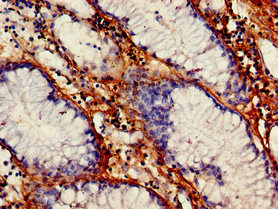

Immunohistochemistry of paraffin-embedded human endometrial cancer using CSB-PA025834LA01HU at dilution of 1:100